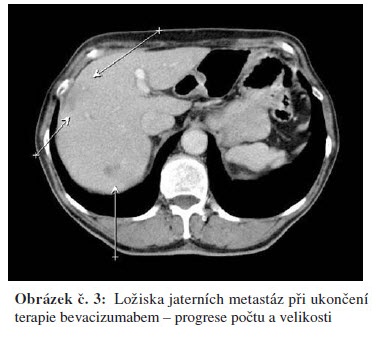

Po korekci hypertenze v říjnu 2008 zahájena chemoterapie FOLFOX 4 + bevacizumab. Kontrolní restaging po 6.s. chemoterapie v lednu a únoru 2009 ukázal parciální regresi jaterního postižení s normalizací hodnot CEA. Postižení nadále nevhodné pro chirurgické řešení a RFA. Pacient nadále bez proteinurie, hypertenze na monoterapii ACEI a stále přiměřená hematologická tolerance. Největší obtíží pacienta bylo ošetřování stomie při diarhoe dobře reagující na terapii loperamidem (Imodium®) nebo diphenoxylatem s atropinem (Reasec®). Jednou podán pouze bevacizumab pro nežádoucí účinky chemoterapie – průjmy. Vzhledem k výbornému stavu pacienta rozhodnuto pokračovat v další chemoterapii. Po dalších 3 měsících v květnu 2009 proveden restaging se stabilizací CT nálezu jaterních metastáz a trvající regresí CEA. Pacient nadále bez výraznějších toxicit, hypertenze nadále na monoterapii ACEI, bez proteinurie, hematologická tolerance přiměřená a diarhoe reagující na Reasec (diarhoe hodnotíme jako nežádoucí účinek flurouracilu). Vzhledem k dobrému stavu pacienta PS 1 opět rozhodnuto pokračovat v další chemoterapii. Po dalších 3 měsících restaging s trvající parciální regresí a nadále pokračováno v chemoterapii. V září 2009 pro vyčerpání pacienta při PS 2 pokračováno dále v monoterapii bevacizumabem. V říjnu 2009 na kontrolním CT hrudníku, břicha a pánve progrese onemocnění, dále progrese CEA a terapie bevacizumabem ukončena. Celkem podáno 20 serií Avastinu v režimu à 14 dnů (v kombinaci s FOLFOX 4 nebo samostatně).